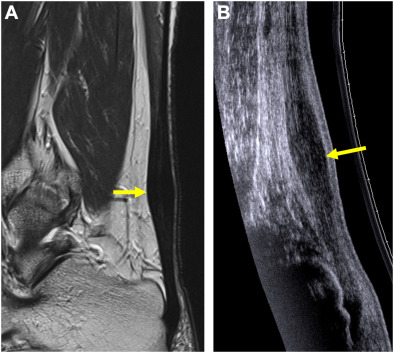

MR imaging and ultrasound of metatarsalgia: the lesser metatarsals.

Radiol Clin North Am. 46 (): 1061-1078

The plantar plate of the lesser metatarsophalangeal joints: potential for injury and role of MR imaging.

Magn Reson Imaging Clin N Am. 9 (): 659-669McCarthy C.L. Thompson G.V.

Ultrasound findings of plantar plate tears of the lesser metatarsophalangeal joints.

Skeletal Radiol. 50: 1513-1525Umans H. Srinivasan R. Elsinger E. et al.

MRI of lesser metatarsophalangeal joint plantar plate tears and associated adjacent interspace lesions.

Skeletal Radiol. 43: 1361-1368